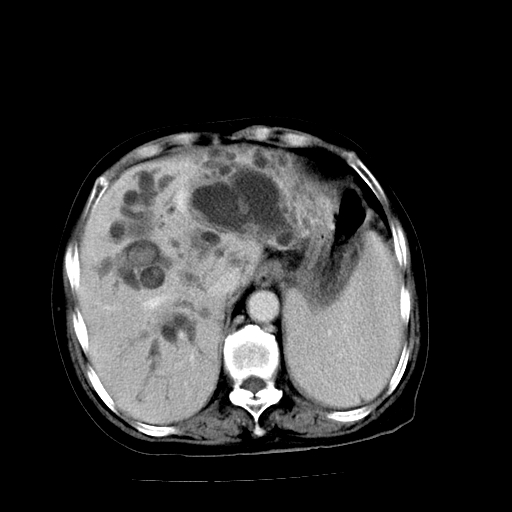

以下是引用卜一在2009-4-7 5:06:00的发言:[br]左右肝内胆管结石伴扩张合并胆系感染;不除外胆管细胞癌可能。支持! [br] [br]

以下是引用随光逐影在2009-4-7 8:21:00的发言:[br]肝内外胆管多发性结石并肝内外胆管扩张;胆系感染。